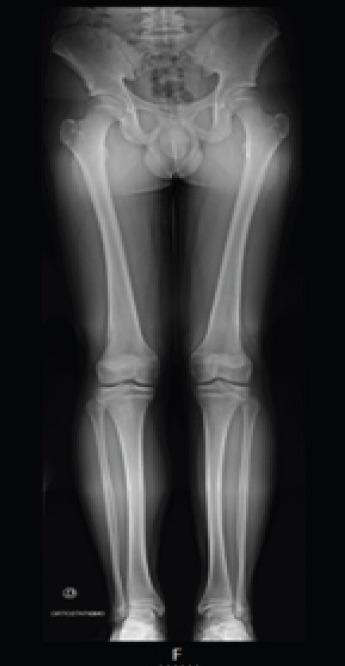

A 6-year-old boy with went to the emergency department after suffering trauma in his left knee. In the performed X-ray, no osteoarticular injury was identified. Conservative treatment with immobilization with cast was performed. After removing the immobilization, the initial evolution was positive with no pain on mobilization. A few months later, he went again to the emergency department due to new left knee trauma. On examination, he had pain in the mobilization of the left knee, especially in knee extension which was not entire. Image study led to the diagnostic of avulsion fracture of the anterior tibial spines. The fracture was classified as modified Meyers and Mckeever Type II and conservative treatment with cast immobilization was performed. In the clinical and imaging revaluation done 4 weeks later, an evolution to non-union of the anterior tibial spine was noticed. At arthroscopy, non-union of tibial spines was confirmed, with elephant paw bone fragment with loss of its right to domicile. Open surgery was performed with debridement, cruentation, and fixation of the bone fragment to the tibia with a screw. The patient had favorable post-operative evolution with fracture consolidation, preserved mobility, no instability of the joint, and no limitation in daily and school activities. Four years after the initial surgery, a second procedure was performed for the removal of the screw. During 7 years of follow-up, no limitations or sequels were found.

一名6岁男孩左膝受伤后前往急诊科。在进行的X线检查中,未发现骨关节损伤。采用石膏固定进行保守治疗。去除固定后,最初的恢复情况良好,活动时无疼痛。几个月后,他因左膝再次受伤再次前往急诊科。检查时,他左膝活动时疼痛,尤其是在不完全伸直时。影像学检查诊断为胫骨前棘撕脱骨折。该骨折被分类为改良迈尔斯和麦基弗II型,并再次采用石膏固定进行保守治疗。在4周后进行的临床和影像学复查中,发现胫骨前棘出现骨不连。关节镜检查证实胫骨棘骨不连,有象爪状骨块且失去原位。进行了开放手术,包括清创、植骨,并使用螺钉将骨块固定于胫骨。患者术后恢复良好,骨折愈合,活动度保留,关节无不稳定,日常和学校活动无受限。初次手术后四年,进行了第二次手术取出螺钉。在7年的随访中,未发现任何限制或后遗症。